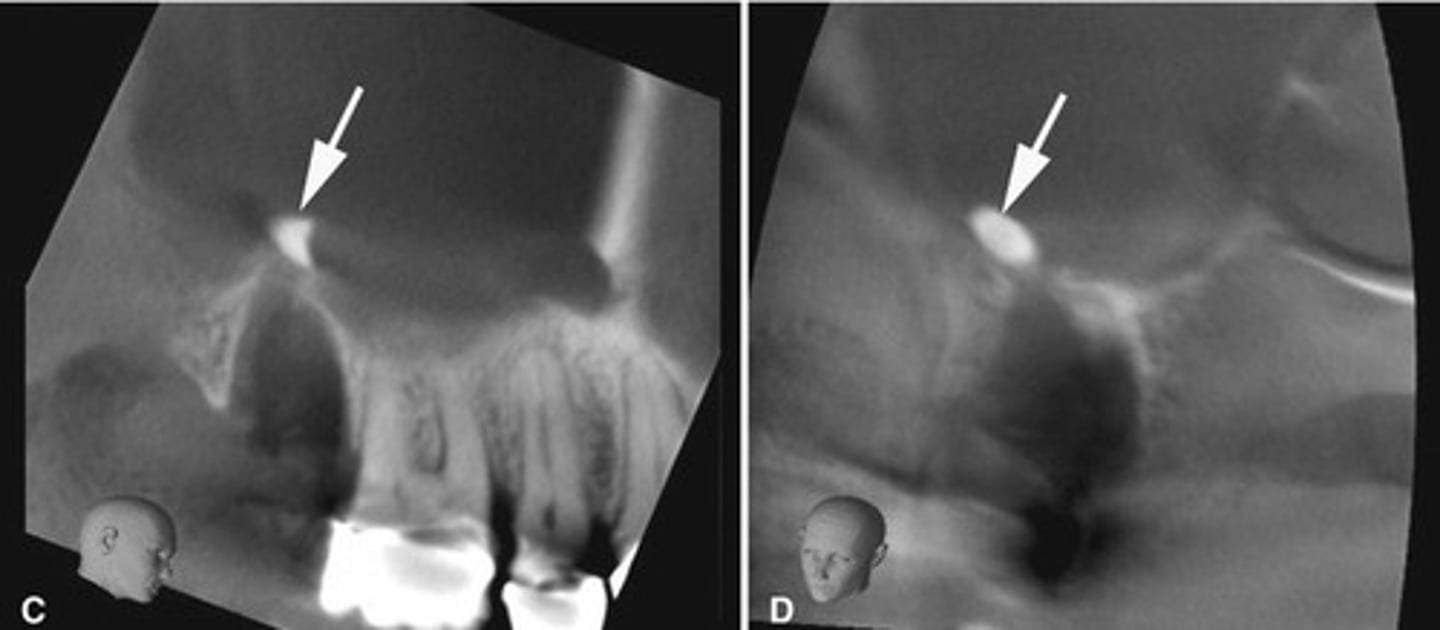

Root tip dislodged into the maxillary sinus.

You can see the PDL

How can you differentiate this from an antroliths in the maxillary sinus?

Root fragment dislodged into the maxillary sinus, this has implications for maxillary posterior extractions.

Maxillary sinus perforation causing mucosal thickening.

Endodontic materials into the maxillary sinus causing mucosal thickening.